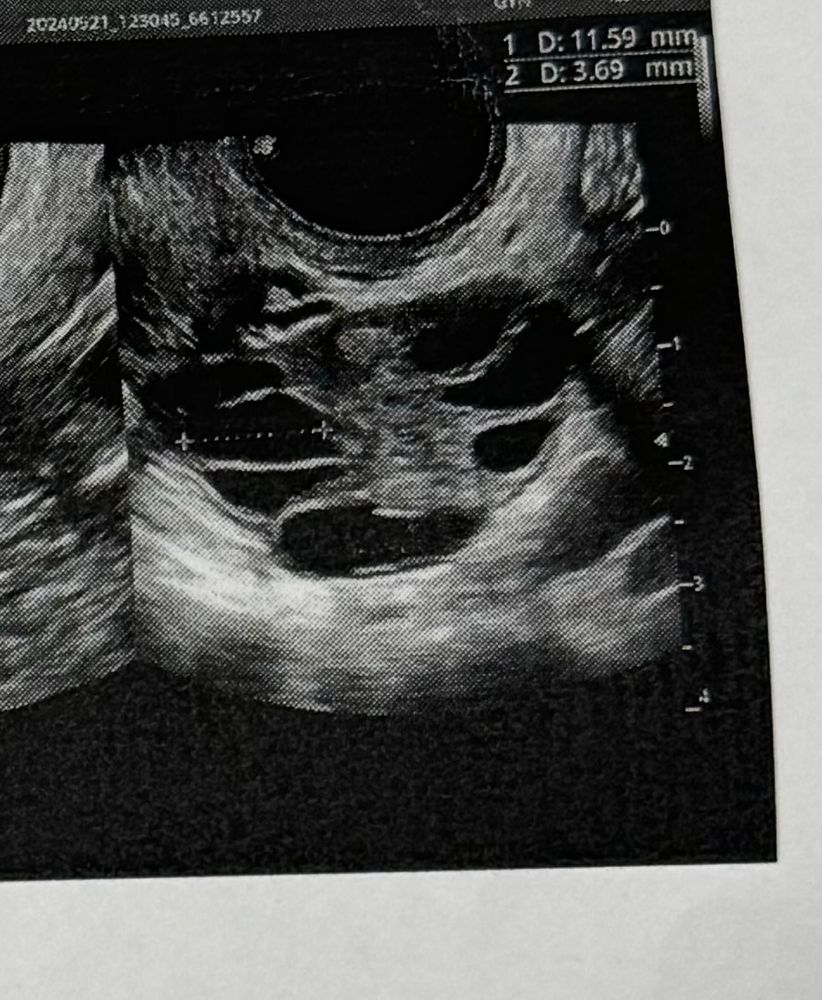

Девочки это нормальная картина на 9 дц?

У меня обычно на 9 дц уже ДФ 16-17 мм был и остальные маленькие, и овуляция обычно на 12-13день.

А тут все фолики примерно одного размера(до 11 мм)

еще и эндометрий 2,5 мм 🗿 что не так с этим циклом